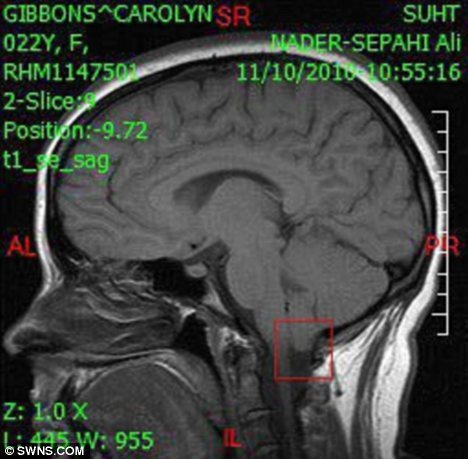

Kondisi ini diakibatkan oleh

penyakit langka yang disebut Chiari Malformation Arnold,dimana volume otak yang

dimilikinya terlalu besar untuk tengkorak kepalanya.

Setiap harinya Corolyn

harus berjuang dari penderitaannya karena setiap gerakan yang tiba-tiba akan

memberi tekanan pada kepalanya yang akan menekan bagian atas tulang belakangnya

dan ini berpotensi menimbulkan kematian.Untuk mencegah penyakitnya agar tidak menjadi

fatal,Carolyn harus rela untuk tidak menonton acara komedi,dan untuk mengurangi

rasa sakitnya,wanita yang berpropesi sebagai guru ini harus mengkonsumsi 50

jenis obat setiap harinya.